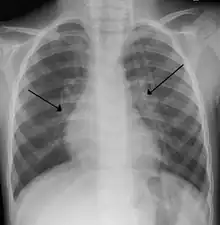

Imaging findings

Chest X-rays findings in children with RSV bronchiolitis are generally nonspecific and include perihilar markings, patchy hyperinflation, and atelectasis.[18] However, the American Academy of Pediatrics (AAP) does not recommend routine imaging for children with presumed RSV bronchiolitis because it does not change clinical outcomes and is associated with increased antibiotic use.[18][5] Chest X-ray is sometimes considered when the diagnosis of bronchiolitis is unclear or when there is an unexpected worsening.[5] In adults with RSV infection, chest films are often normal or demonstrate nonspecific changes consistent with viral pneumonia, such as patchy bilateral infiltrates.[45]